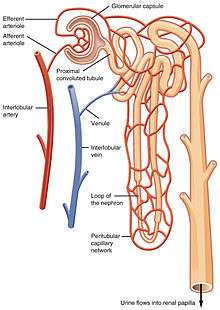

Blood is carried out of the glomerulus by an efferent arteriole instead of a venule, as is observed in most other capillary systems.[2] This provides tighter control over the blood flow through the glomerulus, since arterioles dilate and constrict more readily than venules, owing to arterioles' larger smooth muscle layer (tunica media).

Efferent arterioles of juxtamedullary nephrons, the 15% of nephrons closest to the medulla, send straight capillary branches that deliver isotonic blood to the renal medulla. Along with the loop of Henle, these vasa recta play a crucial role in the establishment of the nephron's countercurrent exchange system.

The efferent arteriole, into which the glomerulus delivers blood, empties into an interlobular vein.

Filtrate drainage

The filtrate that has passed through the capillaries of the glomerulus enters Bowman's capsule. From there, it leaves the corpuscule by a proximal convoluted tubule and enters the collecting duct system of the nephron.[1]